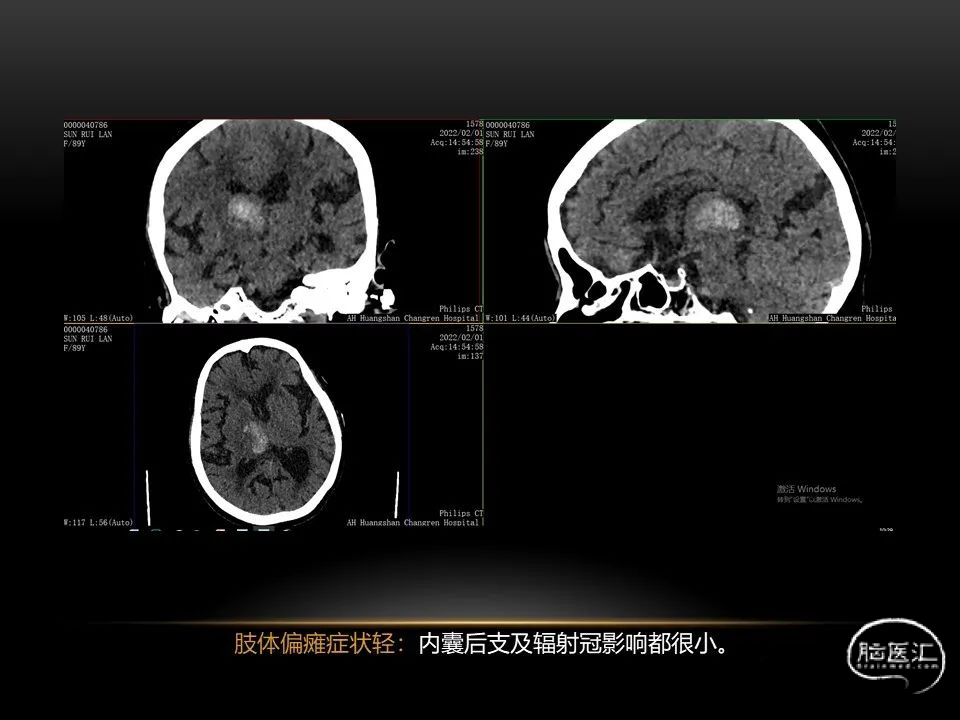

自发性脑出血不仅仅累及内囊后肢才会出现偏瘫及偏身感觉障碍,病变累及大脑脚或辐射冠同样有可能有类似症状和体征。内囊、辐射冠、大脑脚等结构之间是延续的,只是不同区域不同名称而已。定位诊断需要对解剖结构概念清晰,读片准确辨认,灵活掌握。